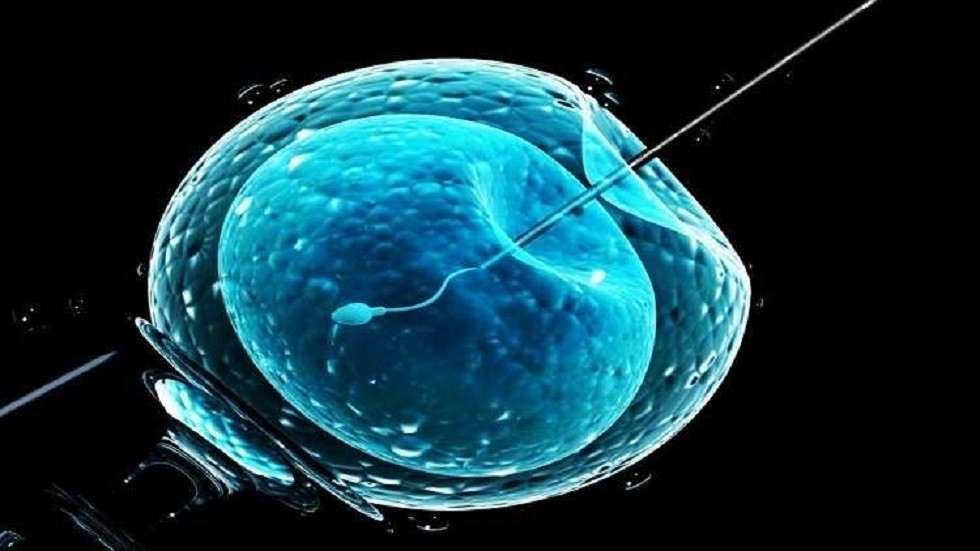

عملية أطفال الأنابيب في تركيا أصبحت الأن واحدة من أشهر العمليات التي تجرى، وذلك لأن تركيا حاليًا تشتهر بالتطور الهائل في المجالات الطبية عامة، ولا شك أن عمليات أطفال الأنابيب تجذب ألاف الأشخاص الحالمين بتحقيق حلم الانجاب.

تعد عملية أطفال الأنابيب في تركيا حل سحري لمشاكل الخصوبة المستعصية عند كلا الجنسين، وذلك لان فرص الحصول على حمل من خلال هذه العملية فرص عظيمة، فلقد أثبتت هذا العملية فاعليتها بمعدل انجاب يتخطى 50% لدى النساء دون سن الأربعين.

تعد هذه العملية الخيار المناسب لدى الذين حاولوا حل مشكلات العقم لسنوات وبسوائل متعددة ولكن دون فائدة، حيث أنها تقوم بحل مشكلات مختلفة بما فيها المشكلات الجينية، ويعد هذا النوع من العمليات هو النمط الاكثر حداثة في مجال العلاج المتاح لحل مشاكل الخصوبة وتأخر الانجاب

هناك عدة خطوات تخضع لها عملية الحقن المجهري في تركيا، وتشترك جميع المراكز الطبية في هذه الخطوات، والخطوات كما يلي: